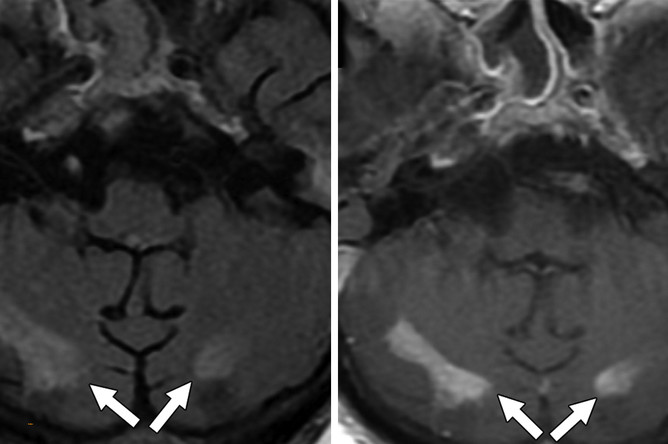

Из 2820 пациентов с COVID-19, с которыми имели дело авторы работы в период с 1 марта по 18 июня 2020 г., 59 прошли МРТ головного мозга. У многих наблюдались признаки поражения мозга, вызванные рассеянным склерозом, инсультами, нехваткой кислорода в крови, недостаточным кровоснабжением мозга и прочими факторами. Но также исследователи заметили, что у шести пациентов (10,2%) имелись признаки лейкоэнцефалопатии.

«Мы наблюдали обширное слияние очагов поражения белого вещества (с характеристиками и расположением, нетипичными для других причин), микрогеморрагическим кровоизлиянием, с ограниченной диффузией, — пишут исследователи.